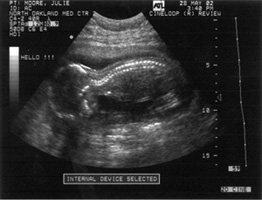

10/04/02        07/18/78

19 weeks         37 1/2 weeks